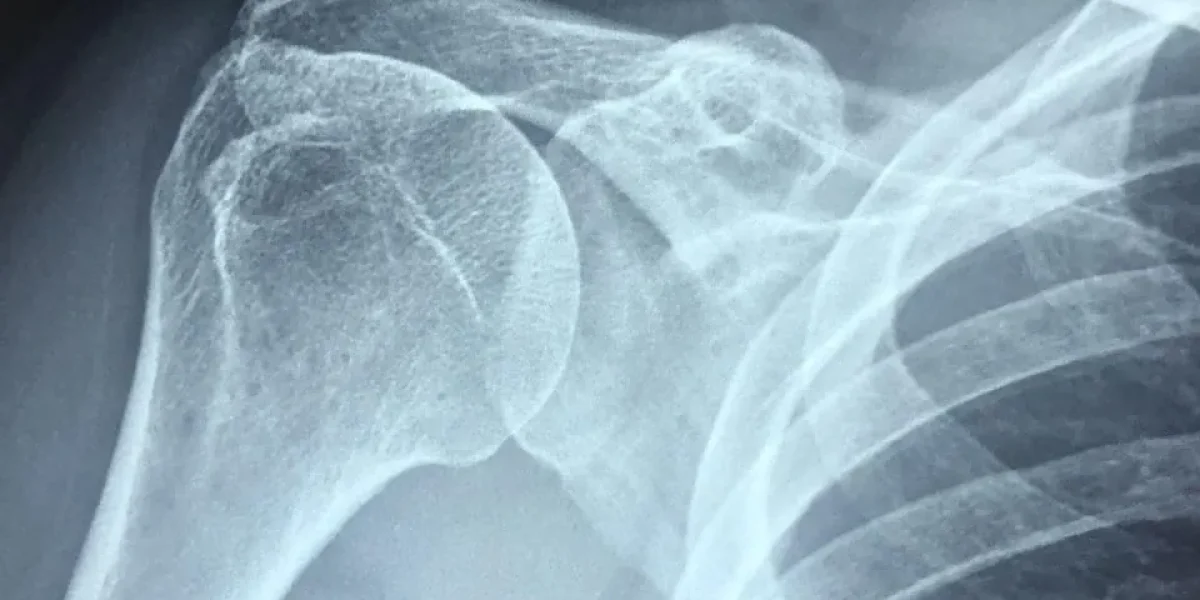

Cervical radiculopathy and shoulder pain occur together when a herniated disc or bone spur compresses C5, C6, or C7 nerve roots. The pain doesn’t stay localized to the neck—it travels along the nerve pathway into the shoulder, mimicking rotator cuff injury or bursitis.

A herniated disc at C5-C6 compresses the C6 nerve root, sending pain directly into the shoulder. Cervical radiculopathy and shoulder pain often coexist because the nerve supplies both regions. Studies show up to 30% of patients initially diagnosed with “shoulder problems” actually have cervical spine pathology as the primary pain generator.

The C5-C6 disc compresses the C6 nerve root, which supplies the deltoid muscle and biceps, creating deep aching shoulder pain. Cervical radiculopathy and shoulder pain present together, making an accurate diagnosis challenging without an MRI.